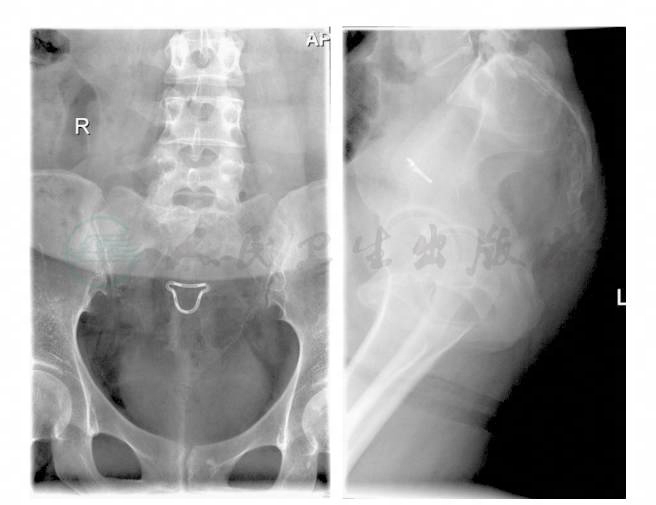

女性,27岁,因“腰背痛半年,加重伴左下肢疼痛2天”入院。患者自述,半年前无明显诱因出现腰部酸胀不适,间歇性加重,无下肢放射痛,卧位翻身及行走时加重,平卧休息后略缓解。2天前症状加重,并出现左下肢放射痛。于当地医院就诊,X线片见骶骨破坏(图1),CT及MRI显示:骶骨肿瘤(图2),转来我院。患者自发病来,大小便正常。既往体健。入院查体:腰椎活动受限,四肢感觉肌力正常,上下肢肌力Ⅴ级,左膝腱反射( + + ),右膝腱反射( + ),双Babinski征(-)。

图1 X线片见骶骨破坏

图2 骶骨破坏,部分残留骨嵴

患者入院后,先行CT导引下病灶穿刺活检,病理报告显示:(骶骨)由单核的梭形细胞和散在分布的多核巨细胞构成的肿瘤,意见为骨巨细胞瘤(Ⅱ级)。因为经济上的原因,患者放弃治疗。